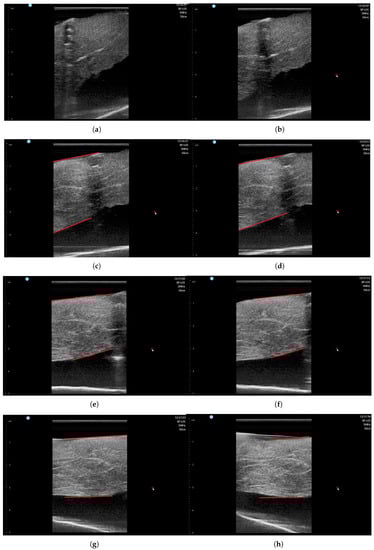

| Angle (°) | 50 | 60 | 70 | 80 | 90 | 100 | 110 | 120 | Average | Std. Deviation | |

|---|---|---|---|---|---|---|---|---|---|---|---|

| Operator #1 | muscle thickness (mm) | - | - | 27.54 | 26.41 | 24.52 | 24.53 | 26.41 | 26.43 | 25.97 | 1.09 |

| muscle thickness - average value (mm) | - | - | 1.57 | 0.44 | −1.44 | −1.43 | 0.44 | 0.46 | |||

| Operator #2 | muscle thickness (mm) | - | - | 27.47 | 26.45 | 24.9 | 24.56 | 26.11 | 26.22 | 25.95 | 0.97 |

| muscle thickness - average value (mm) | - | - | 1.51 | 0.49 | −1.05 | −1.38 | 0.15 | 0.27 | |||

| Operator #3 | muscle thickness (mm) | - | - | 27.73 | 26.86 | 24.56 | 24.64 | 25.84 | 25.47 | 25.85 | 1.14 |

| muscle thickness - average value (mm) | - | - | 1.88 | 1.01 | −1.28 | −1.21 | 0.00 | −0.38 | |||

| Operator #4 | muscle thickness (mm) | - | - | 27.73 | 27.16 | 24.9 | 25.66 | 25.84 | 26.22 | 26.25 | 0.94 |

| muscle thickness - average value (mm) | - | - | 1.47 | 0.91 | −1.35 | −0.59 | −0.40 | −0.03 | |||

| Average | muscle thickness (mm) | - | - | 27.62 | 26.72 | 24.72 | 24.84 | 26.05 | 26.08 | 26.01 | 1.00 |

| muscle thickness - average value (mm) | - | - | 1.61 | 0.71 | −1.28 | −1.16 | 0.04 | 0.07 | |||